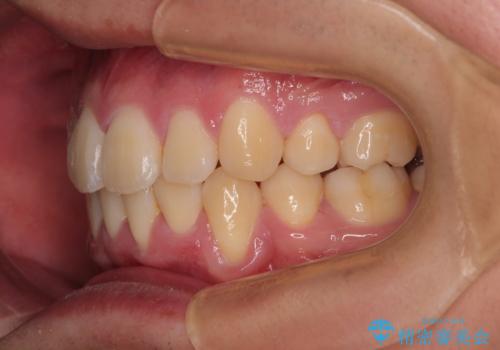

移動が順調に進み、1年半の短期間で治療を終えることができました。

前方に突出した上顎前歯の傾斜も改善されました。